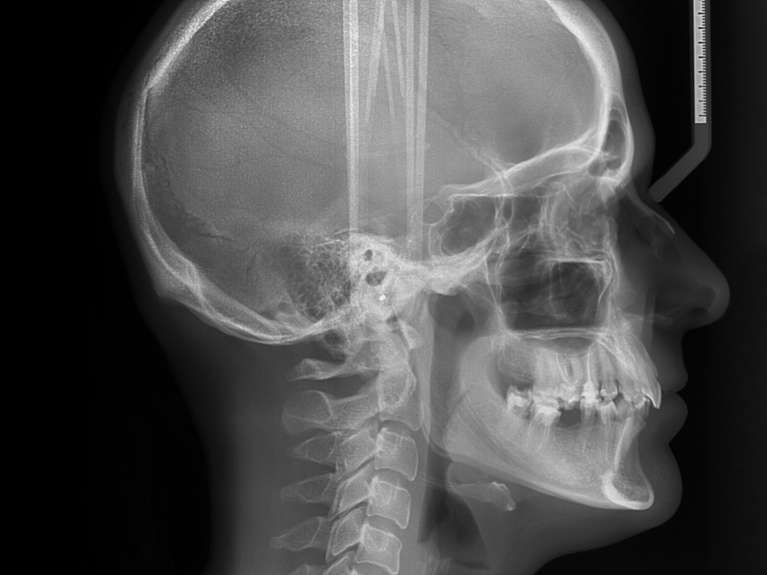

Ceph X-Ray

A cephalometric X-ray provides a side view of your mouth and jaw joints. It can be helpful for orthodontic treatment planning and diagnosing jaw joint issues.